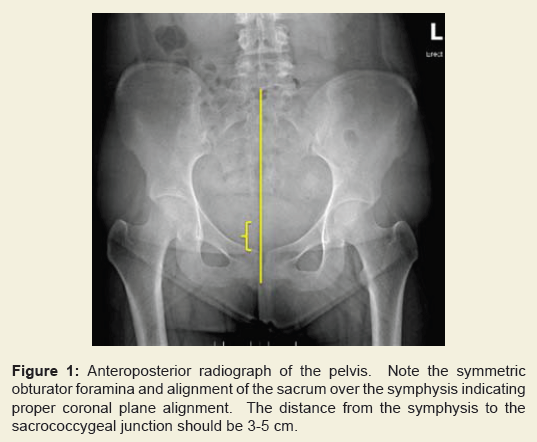

When evaluating hip arthritis, three weight-bearing radiographs are essential to determine the severity of hip disease, and allow for visualization of the functional joint space. Proper radiographic technique must be utilized in obtaining all hip radiographs. The use of a radiopaque marker of known size (e.g. 25 mm) can be helpful in preoperative templating, should surgical treatment be indicated. Care should be taken to ensure that the marker is placed as close as possible to the femoral head in the anteroposterior plane to avoid magnification error.The first radiograph that should be examined is the AP radiograph of the pelvis. It is important to be able to assess the quality of the image. The lower extremities should be positioned in approximately 15 degrees of internal rotation, which decreases the femoral anteversion (usually 12-15 degrees) and allows for better visualization of the femoral neck [15]. One must ensure proper sagittal and coronal alignment of the radiograph to confirm there is no malrotation of the pelvis. Measurement of the distance from the sacrococcygeal junction to superior symphysis pubis indicates proper sagittal pelvic rotation and is normally between 3 and 5 cm [16]. In addition, the center of the sacrum should be in line with the symphysis pubis and the obturator foramina should be symmetric resulting in proper coronal plane rotation (Figure 1).